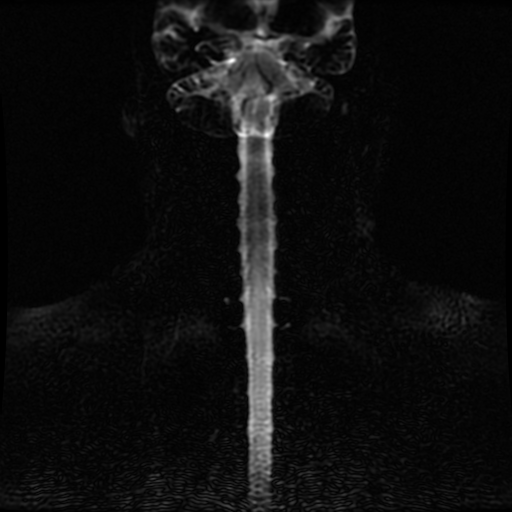

Se observa perdida de la lordosis normal de la columna cervical.

Se observa hipo intensidad del ligamento longitudinal anterior y posterior de la columna cervical, también se observa perdida de la movilidad y rigidez de la misma, los ligamentos interespinosos se ven hipointensos en T2 y en T1, al igual que el pliegue nucal, lo que sugiere calcificación de estas estructuras anatómicas.

Se observa fusión de las vertebras cervicales 5-6 y 6-7, dando la apariencia de bambú.

• Perdida de la lordosis

• Ligamentos espinales anterior, posterior, interespinosos y pliegue nucal calcificados

• Fusión de vertebras cervicales 5-6 y 6-7.